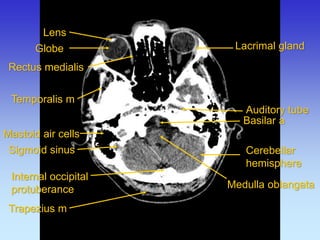

Lens

Globe

Auditory tube

Lacrimal gland

Mastoid air cells

Medulla oblangata

Rectus medialis

Temporalis m

Cerebellar hemisphere

Trapezius m

Sigmoid sinus

Basilar a

Internal occipital protuberance